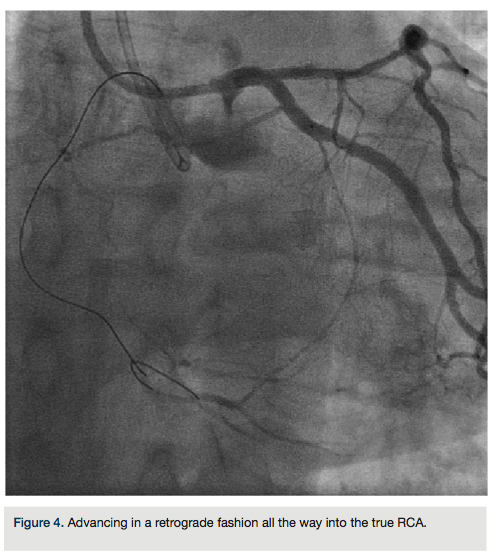

heparin to achieve an ACT >300, we went from the left system with a Runthrough wire (Terumo) and an over-the-wire balloon, using the workhorse wire to wire the circumflex. We then changed to a retrograde crossing wire, the Asahi Fielder FC (Abbott Vascular), to wire into the collateral going to the distal RCA (Figure 3) and were able to advance in a retrograde fashion all the way into the true RCA (Figure 4). We backed out the 1.5 mm balloon and trapped it in the guide with a 2.5 x 20 Emerge (Boston Scientific), inflated to 16 atmospheres. We exchanged out initially for a Corsair catheter (Asahi Intecc) and advanced retrograde into the